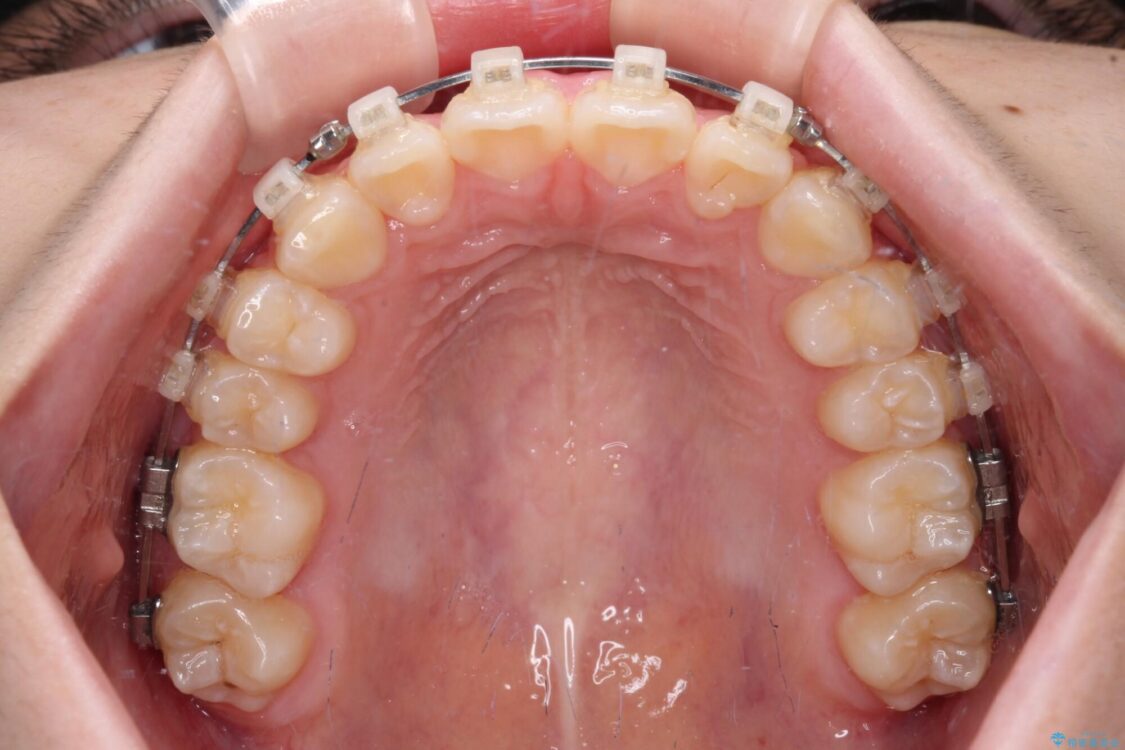

治療途中

• インビザラインは使える自信がない ワイヤー装置にて矯正治療 治療途中画像